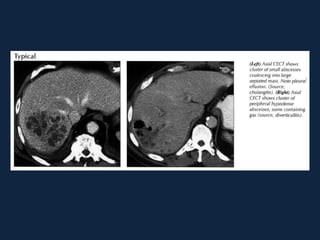

Abscessos Piogênicos

 S/C                 Fase portal

 Fase arterial         Fase portal

 Fase tardia

Abscessos Piogênicos ►s/c: Lesãogrosseiramente arredondada, hipodensa (0-45 HU), podendo conter septações e gás (sinal específico, presente em menos de 20% dos casos). Pode haver nível ar-fluido e fluido-debris. ►Realce anelar e/ou das septações após a administração do contraste. ►Pode haver derrame pleural e atelectasia de lobo inferior direito.

Abscessos Piogênicos  Fasearterial  Fase portal

Abscessos Piogênicos  Fase tardia